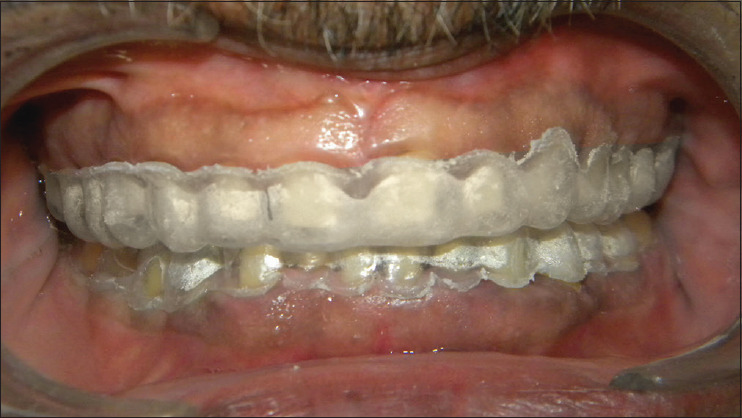

Prosthetic rehabilitation in multifaceted dental abnormality needs sequential planning to ensure adaptation of oral and associated musculature. Reduction of tooth structure before adaptation of oral and associated components may complicate the treatment modality if compliance of the musculature is poor. Hence, the fabrication of over-provisional in esthetic rehabilitation enables to assess of the success of the treatment plan preoperatively before invasive trials. A 55-year-old male with a diagnosis of Category I loss of vertical dimension, according to Turner and Missirlian classification, required full mouth rehabilitation. The case report depicts the preoperative management of full mouth rehabilitation with direct chair-side technique using over-provisional to analyze the esthetic and functional changes. Restoration of esthetics is a complex task that needs patient satisfaction to achieve success. Over-provisional is a simplified method of establishing esthetics and functional rehabilitation. Esthetic and functional rehabilitation of an individual can be an easy transition when preoperative evaluation of the final prosthesis design is visually created intraorally.